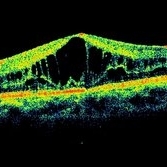

Inherited Cystoid Macular Edema

Inherited Cystoid Macular Edema

May 4 2014 by Mallika Goyal, MD

Left eye OCT of a 30-year-old male patient with bilateral inherited cystoid macular edema. There is no history of diabetes, hypertension, ocular surgery and there is no family history of similar eye problem. There is no fluorescein leakage at the macula as might be anticipated in an eye with cystoid macular edema.

Photographer: Mallika Goyal, MD, Apollo Health City, Jubilee Hills, Hyderabad, India

Condition/keywords: cystoid macular edema (CME), optical coherence tomography (OCT)